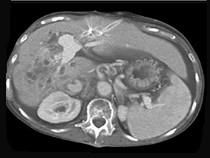

问题 男,50岁,右上腹痛,进行性黄疸,无腹部包块,AFP阴性,影像检查如图,最可能的诊断是()

选项 A.肝细胞肝癌 B.胆管癌 C.肝血管瘤 D.肝腺瘤 E.肝转移瘤

答案 B